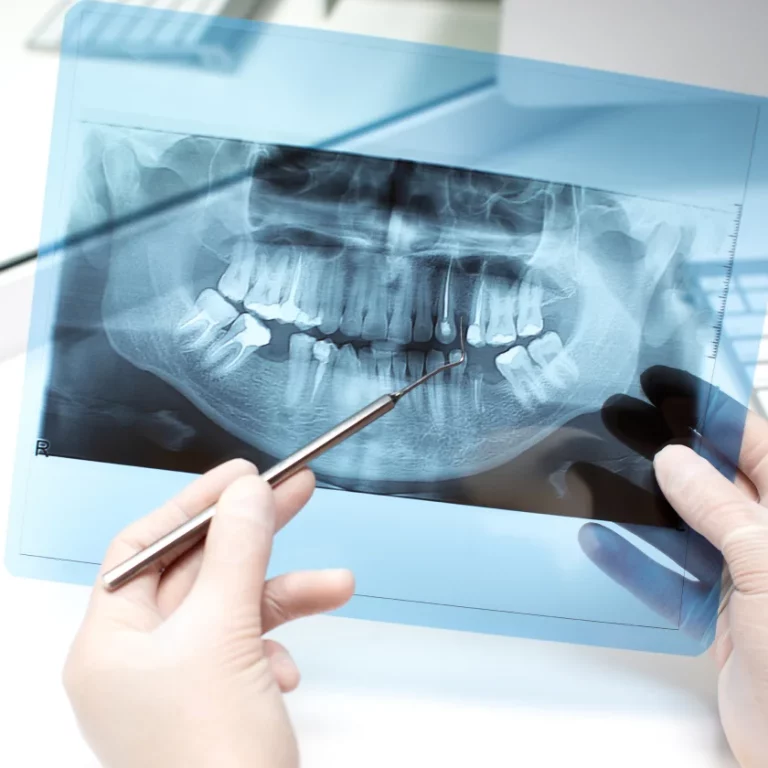

Root canals are an incredible treatment option that effectively combats infection without the need for a tooth extraction.